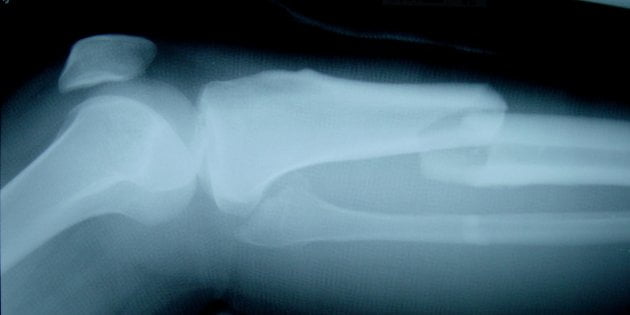

Amerikaanse onderzoekers hebben een centimeter verwijderd bot opnieuw laten groeien. Hiervoor gebruikten ze een raster gemaakt van composiet, afkomstig uit de luchtvaart.

Het experiment ging als volgt. De onderzoekers verwijderden een centimeter bot uit het dijbot van een proefrat. Daarna plaatsten ze een staafje tussen de twee botdelen om deze bij elkaar te houden. Hier werd poreus composietmateriaal omheen gewikkeld. Bot en bloedvaten groeiden door dit raster heen tot het bot was geheeld.

Toekomst voor de methode ziet Wooley vooral in de behandeling van gewonde soldaten en verkeersslachtoffers. Volgens de wetenschapper kan de techniek vele amputaties voorkomen.